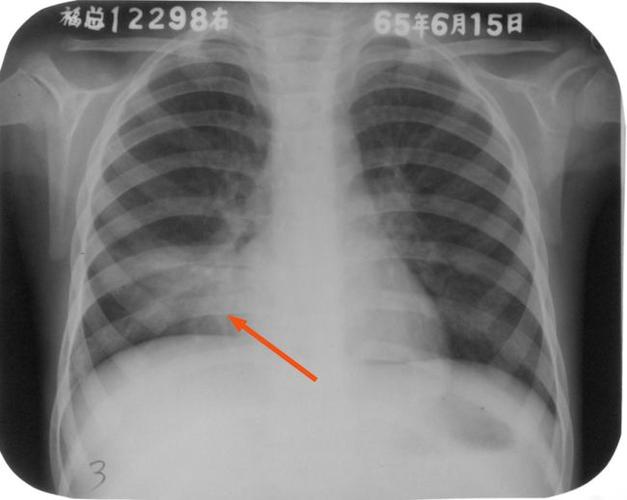

胸片显示右下肺炎有轻度的浸润病灶